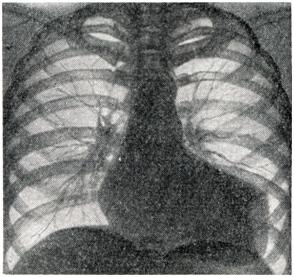

Полуовальное выпячивание по левому контуру левого желудочка. Видна «зарубка» на верхней границе аневризмы (рентгенограмма).

Рентгенодиагностика аневризмы сердца начала развиваться в двадцатых годах 20 в. [Кристиан, Фрик (Н.А. Christian, H.Frick), 1922] и продолжает совершенствоваться, обогащаясь новыми методиками, и. все же распознавание этого заболевания представляет значительные трудности. Для диагностики аневризмы сердца необходима многопроекционная рентгеноскопия с тщательным изучением особенностей сокращений сердца с целью выявления свойственных аневризмам зон акинезии («немых зон») и дискинезии (парадоксальной пульсации). Кроме рентгенограмм в прямой и косых проекциях, рекомендуются рентгенограммы с небольшим поворотом больного (на 20 — 30°) как в правое, так и в левое косое положение. В тех же проекциях производят рентгенокимографию и электрокимографию. Наиболее важным признаком мешковидной аневризмы сердца служит полуовальное выпячивание на контуре левого желудочка (рис. 2 и 3), отграниченное с обеих сторон «зарубками». Для большой аневризмы сердца характерно резкое увеличение поперечника сердечной тени. Левый контур сердца при этом нередко имеет прямоугольные очертания (рис. 4.). Эти грубые морфологические признаки непостоянны и часто отсутствуют при диффузных аневризмах. Поэтому большое значение приобретает симптом волнистости контура, то есть слабо выраженные, иногда едва заметные плоские выпячивания. Роль этих признаков резко возрастает, если соответственно такому выпячиванию наблюдаются и нарушения контрактильных свойств миокарда в виде неподвижности контура или парадоксальной пульсации. Следует учесть, что прослеживание феномена парадоксальной пульсации по заднему контуру левого желудочка во втором косом и боковом положениях может наблюдаться и в норме вследствие систолического преобразования формы сердца. Иногда по контуру левого желудочка видны небольшие углообразные деформации контура (сращения перикарда). В распознавании функциональных признаков аневризмы сердца большое значение имеет рентгеноскопия, но для детального изучения необходима графическая запись движений сердечного контура — рентгенокимография и электрокимография. На рентгенокимограммах отчетливо определяются зоны акинезии, их локализация и протяженность. При сопоставлении рентгенокимограмм аорты и сердца обнаруживаются несвоевременные — парадоксальные (в систоле — кнаружи) смещения контура в области аневризмы сердца, а иногда также признаки резких пассивных смещений истонченной фиброзной стенки аневризмы сердца в виде «оторванных сегментов» сердечной тени или парадоксальной поперечном полосатости сердечной тени (М. А. Иваницкая, 1950). Преимуществом электрокимографии является возможность более точного анализа йарушений контрактильности миокарда: при записи движений контура левого желудочка в области аневризмы сердца определяется подъем кривой во время систолы вместо спуска ее в норме, причем одновременная запись электро- или фонокардиограммы позволяет точно установить время возникновения этого парадоксального движения, продолжительность и амплитуду его по отношению к общей амплитуде кривой. Различают полную парадоксальную пульсацию контуров аневризмы, когда движение в систоле кнаружи занимает всю систолу (это особенно резкие нарушения контрактильности миокарда), и частичную парадоксальную пульсацию, когда это движение занимает лишь часть систолы; при этом зубец как электрокимографической, так и рентгенокимографической кривой приобретает дополнительную вершину. Большое значение для распознавания аневризмы сердца имеет рентгенокимография, обеспечивающая одновременное изучение морфологических и функциональных признаков. Функциональные рентгенологические признаки облегчают диагноз плоских, диффузных аневризм, не дающих выразительном морфологической картины. Для выявления верхушечной аневризмы сердца рекомендуется исследование при глубоком вдохе или с раздуванием желудка. Аневризмы нижней стенки левого желудочка не распознаются при обычном рентгенологическом исследовании. Наиболее точную морфологическую и функциональную характеристику аневризмы сердца в настоящее, время обеспечивает киновентрикулография [Горлин (R. Gorlin), 1967], с помощью которой ныинляются аневризмы любой локализации. Сравнение данных комплексною рентгенологического исследования сердца до и после операции позволяет дать объективную оценку результатам хирургического лечения аневризмы сердца. Использование современных специальных методов исследования позволило повысить частоту прижизненной диагностики аневризмы сердца, что имеет большое практическое значение в связи с успехами хирургического лечения этого заболевания. Аневризма сердца относится к прогностически неблагоприятным осложнениям инфаркта миокарда. Многочисленные отечественные и зарубежные статистики показывают, что спустя 5 лет после инфаркта миокарда, осложненного аневризмой, в живых остаются не более 12% больных. В первые 3 года после инфаркта, осложненного аневризмой, умирают 73%, а через 5 лет — 88% больных, в том числе от сердечной недостаточности — 70% и от тромбоэмболических осложнений — 30%, хотя имеются отдельные указания о продолжительности жизни больных до 10 и более лет. Другими осложнениями, приводящими к смерти больных аневризмой сердца, являются повторные инфаркты и реже — разрывы аневризмы. Поэтому в настоящее, время консервативное лечение следует использовать только для борьбы с осложнениями и как подготовку к операции. Оперативному лечению подлежат: 1) больные с хроническими аневризмами сердца, осложненными сердечной недостаточностью, стенокардией, аритмией, неподдающиеся консервативной терапии; 2) больные с аневризмой сердца, осложненными тромбозом мешка или его прогрессивным увеличением, грозящим разрывом. Только у некотоорых больных с небольшой неосложненной диффузной или мешковидной аневризмой сердца при стабильном состоянии операцию можно отложить при условии диспансерного наблюдения до изменения клинической картины.Резекция мешковидных аневризм сердца должна производиться не ранее чем через 3—4 месяца после перенесенного инфаркта, то есть когда образуется прочная рубцовая ткань, предупреждающая несостоятельность швов по линии иссечения аневризматического мешка. Исключением являются быстро увеличивающиеся аневризма сердца Операция не должна производиться больным с большой диффузной аневризмой сердца при плохой функции оставшейся части желудочка. Относительным противопоказанием к хирургическому лечению аневризмы сердца является возраст больных — старше 65 лет. В связи с тяжелым состоянием больных и сложностью операций вмешательства при аневризме сердца носили до середины 50-х годов 20 в. случайный характер. В 1931 г. Зауэрбрух (Е. F. Sauerbruch) во время операции на грудной клетке по ошибке вскрыл аневризму правого желудочка, принятую им за опухоль средостения, ушил ее у основания и иссек. В 1942 г. Бек (С. S. Beck) укрепил свободным куском широкой фасции бедра стенку постинфарктной аневризмы левого желудочка, диагностированной дооперации. С 1944 г. при хирургическом лечении хронической аневризмы сердца применяется ряд вмешательств: 1) укрепление истонченной стенки аневризмы различными аутотрансплантатами: грудной мышцей [Д'Аллен (С D. Allen), 1956], большим сальником (В. И. Казанский, 1964), кожным лоскутом [Ниднер (F. F. Niedner), 1955] и др.; 2) погружение аневризмы швами (Б. В. Петровский, Ф. Г. Углов, А. А. Вишневский, 1954 — 1957); 3) погружение аневризмы швами с помощью межреберной мышцы на ножке [Шпачек (В. Spacek), 1954]; 4) резекция аневризмы закрытым способом с использованием игольчатого зажима [Бейли (С. P. Bailey), 1954]; 5) резекция аневризмы на открытом сердце в условиях искусственного кровообращения [Кули, Каткарт, Лиллихей (D. A. Cooley, R. Т. Gathcart, С. W. Lillehei), 1958; Б. В. Петровский]; 6) различные варианты диафрагмопластики — укрепление стенки сердца лоскутом диафрагмы (Б. В. Петровский, 1957). Операция укрепления стенки аневризмы различными тканями применяется в настояшее, время только при диффузной аневризме. При мешковидной аневризме она недостаточна, так как не устраняет парадоксальной пульсации и угрозы разрыва аневризмы. Операция погружения аневризмы сердца швами может применяться лишь при небольших мешковидных аневризмах желудочка или предсердия, случайно выявленных на операции, проводимой по поводу сдавливающего перикардита или ревматических пороков сердца; при аневризмах, осложненных тромбозом, ее нельзя применять из-за опасности эмболии. Прикрытие и погружение аневризмы сердца с помощью межреберной мышцы не нашло широкого применения: ликвидируя парадоксальную пульсацию, это вмешательство не улучшает питания сердечной мышцы. Как показал опыт торакопластики по Абражанову, используемые для пластических целей мышцы всегда рубцово перерождаются; помимо этого, возможна эмболия за счет пристеночных тромбов. Резекции аневризматического мешка закрытым способом относятся к радикальным вмешательствам. Этот метод разработал Бейли, который в 1954 г. выполнил подобную операцию, пережав основание анев¬ризмы специальными клеммами. В дальнейшем пережатие основания аневризмы для предотвращения эмболии он производил только после ее рассечения и удаления пристеночных тромбов. Особое внимание уделяется вымыванию струей крови тромботических масс, что независимо от Бейли предложил Б. В. Петровский для удаления тромбов из ушка и предсердия при операциях по поводу митрального стеноза и аневризмы сердца. Преимущество этого метода состоит в том, что для его выполнения не требуется сложной аппаратуры, он прост и эффективен, а использование вымывания тромбов в какой-то мере служит профилактикой тромбоэмболии. И все же резекция аневризмы сердца закрытым способом, несмотря на меры предосторожности, связана с опасностью возникновения артериальной тромбоэмболии. Этот метод может применяться при резекции небольших мешковидных аневризм, особенно в случаях, когда отсутствуют пристеночные тромбы. Резекция аневризмы сердца открытым способом в условиях искусственного кровообращения нашла широкое распространение во всем мире. Эта операция с успехом была выполнена независимо друг от друга Кули, Каткартом и Лиллихеем в 1958 г. Ее преимущество состоит в том, что можно произвести тщательное удаление тромботических масс, аккуратно иссечь аневризматический мешок, провести ревизию папиллярных мышц, митрального клапана и межжелудочковой перегородки. Большие мешковидные и грибовидные аневризмы следует удалять только этим способом. В мировой литературе описано свыше 500 операций, выполненных при аневризме сердца [Фавалоро (R. Favaloro) — 130, Лиллихей — 126, Кули — 80, Б. В. Петровский — 186, Геберер (G. Heberer) — 6, Бьерк (V. О. Bjork) — 5 и др.]. В СССР первая успешная операция выполнена Б. В. Петровским, им же разработаны (1957) следующие виды операций: 1) пластика диафрагмальным лоскутом на ножке при диффузной аневризме сердца; 2) прошивание основания аневризмы шелковыми швами или танталовыми скобками с помощью аппарата УКЛ-60 при небольших мешковидных аневризмах без тромбоза; 3) резекция аневризмы с удалением тромботических масс из полости желудочка закрытым способом с последующей диафрагмо-пластикой линии шва при мешковидных аневризмах с тромбозом. Диафрагмо-пластика способствует реваскуляризации миокарда путем прорастания сосудов из диафрагмального лоскута в миокард, поскольку такой лоскут на ножке имеет хорошее кровоснабжение и иннервацию. Близкое расположение сердца и диафрагмы, интимные связи их кровоснабжения и иннервации дают основание с успехом использовать диафрагму для пластики стенки сердца. Как показали экспериментальные исследования, этот лоскут очень редко атрофируется, уже через 3—5 месяцев происходит прорастание сосудов диафрагмы в миокард. В клинике с помощью коронарографии доказано наличие густой сети анастомозов между сосудами диафрагмы и сердца через 8 лет после диафрагмопластики (рис. 5).